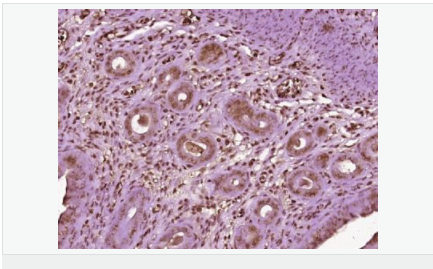

| 產(chǎn)品應用 | WB=1:500-2000 IHC-P=1:100-500 IHC-F=1:100-500 Flow-Cyt=1ug/Test ICC=1:100-500 IF=1:100-500 (石蠟切片需做抗原修復) not yet tested in other applications. optimal dilutions/concentrations should be determined by the end user. |

| 產(chǎn)品介紹 | Estrogen and progesterone receptor are members of a family of transcription factors that are regulated by the binding of their cognate ligands. The interaction of hormone-bound estrogen receptors with estrogen responsive elements(EREs) alters transcription of ERE-containing genes. The carboxy terminal region of the estrgen receptor contains the ligand binding domain, the amino terminus serves as the transactivation domain, and the DNA binding domain is centrally located. Two forms of estrogen receptor have been identified, ER alpha and ER beta. ER alpha and ER beta have been shown to be differentially activated by various ligands. The biological response to progesterone is mediated by two distinct forms of the human progesterone receptor (hPR-Aand hPR-B), which arise from alternative splicing. In most cells, hPR-B functions as a transcriptional activator of progesterone-responsive gene, whereas hPR-A function as a transcriptional inhibitor of all steroid hormone receptors. Function: The steroid hormones and their receptors are involved in the regulation of eukaryotic gene expression and affect cellular proliferation and differentiation in target tissues. Progesterone receptor isoform B (PRB) is involved activation of c-SRC/MAPK signaling on hormone stimulation. Isoform A is inactive in stimulating c-Src/MAPK signaling on hormone stimulation. Subunit: Interacts with SMARD1 and UNC45A. Interacts with CUEDC2; the interaction promotes ubiquitination, decreases sumoylation, and repesses transcriptional activity. Interacts with PIAS3; the interaction promotes sumoylation of PR in a hormone-dependent manner, inhibits DNA-binding, and alters nuclear export. Interacts with SP1; the interaction requires ligand-induced phosphorylation on Ser-345 by ERK1/2 MAPK. Interacts with PRMT2. Subcellular Location: Nucleus. Cytoplasm. Note=Nucleoplasmic shuttling is both homone- and cell cycle-dependent. On hormone stimulation, retained in the cytoplasm in the G(1) and G(2)/M phases. Isoform A: Nucleus. Cytoplasm. Note=Mainly nuclear. Post-translational modifications: Phosphorylated on multiple serine sites. Several of these sites are hormone-dependent. Phosphorylation on Ser-294 occurs preferentially on isoform B, is highly hormone-dependent and modulates ubiquitination and sumoylation on Lys-388. Phosphorylation on Ser-102 and Ser-345 also requires induction by hormone. Basal phosphorylation on Ser-81, Ser-162, Ser-190 and Ser-400 is increased in response to progesterone and can be phosphorylated in vitro by the CDK2-A1 complex. Increased levels of phosphorylation on Ser-400 also in the presence of EGF, heregulin, IGF, PMA and FBS. Phosphorylation at this site by CDK2 is ligand-independent, and increases nuclear translocation and transcriptional activity. Phosphorylation at Ser-162 and Ser-294, but not at Ser-190, is impaired during the G(2)/M phase of the cell cycle. Phosphorylation on Ser-345 by ERK1/2 MAPK is required for interaction with SP1. Sumoylation is hormone-dependent and represses transcriptional activity. Sumoylation on all three sites is enhanced by PIAS3. Desumoylated by SENP1. Sumoylation on Lys-388, the main site of sumoylation, is repressed by ubiquitination on the same site, and modulated by phosphorylation at Ser-294. Similarity: Belongs to the nuclear hormone receptor family. NR3 subfamily. Contains 1 nuclear receptor DNA-binding domain. SWISS: P06401 Gene ID: 5241 Database links: Entrez Gene: 5241 Human Entrez Gene: 18667 Mouse Entrez Gene: 100009094 Rabbit Omim: 607311 Human SwissProt: P06401 Human SwissProt: Q00175 Mouse SwissProt: P06186 Rabbit Unigene: 2905 Human Unigene: 32405 Human Unigene: 742403 Human Unigene: 12798 Mouse Unigene: 437703 Mouse Unigene: 1947 Rabbit Unigene: 10303 Rat Important Note: This product as supplied is intended for research use only, not for use in human, therapeutic or diagnostic applications. |